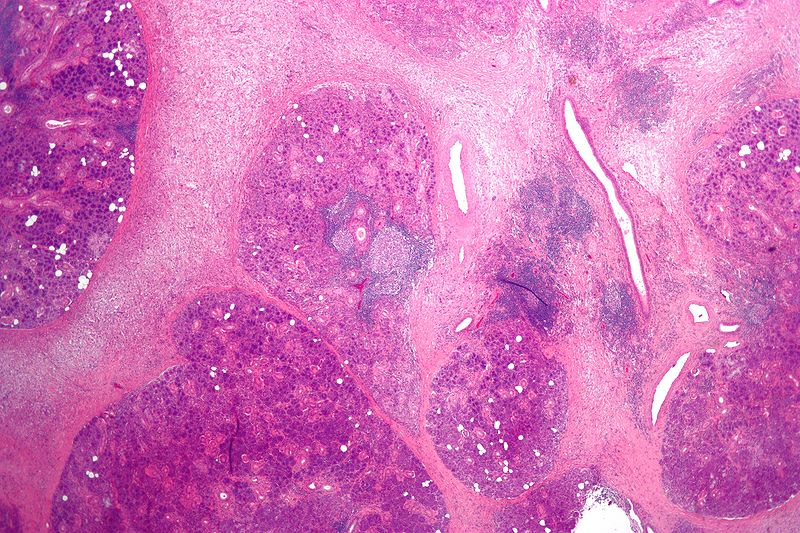

Mucoepidermoid Carcinoma

Mucoepidermoid carcinoma is a malignant tumor made up of squamous and mucin-producing cells.

Mucoepidermoid carcinoma is the most common malignant tumor of the salivary gland.

Mucoepidermoid carcinoma often occurs in the parotid.

The facial nerve is frequently compromised by mucoepidermoid carcinoma.